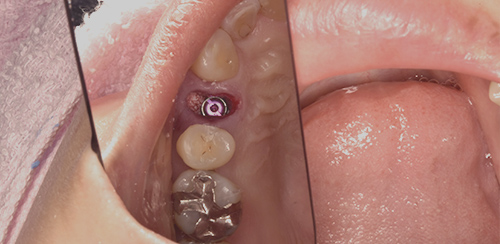

抜歯後

骨を入れた後

通常なら歯茎の横から穴を大きくあけてサイナスリフトという方法で骨をつくり、半年程度待ってインプラントをいれますが、当院ではソケットリフトという方法で、歯茎の横でなく歯があるところから穴をあけ、ソケットリフトという方法で骨を入れそのままインプラントをいれます。

これによって痛みや腫れは最小限にすることができ、治療期間も半分以下の3ヶ月程度にすることができます。

ソケットリフトを入れた図

インプラント治療後